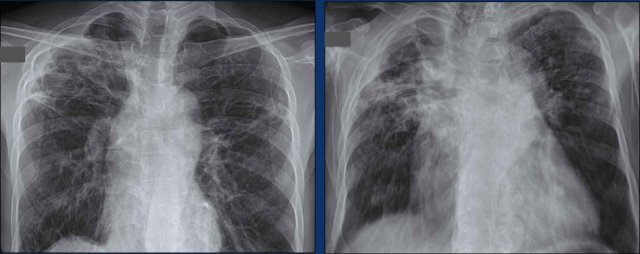

The images show four examples of pleural fluid in patients with TB.

Images

- A 12-year old boy with lethargy, weight loss and chronic cough.

There is left upper lobe consolidation and a large amount of pleural fluid. - Unilateral pleural effusion. Notice also rib abnormalities. These may be a result of TB.

- Large amount of pleural fluid resulting in mediastinal shift and compression of the left lung in a 6-year old boy.

- Large amount of pleural fluid both caudally and cranially of the compressed left lung.